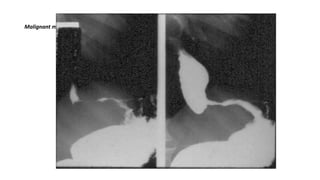

MALIGNANT

LEFT: Small polypoid carcinoma. RIGHT: Large polypoid lesion.

Adenocarcinoma of the distal esophagus.

• A 4 cm segmental narrowing with an irregular margin and shouldering

appearance at the distal half of the esophagus suggests tumoral

infiltration.

• Evidence of prior sternotomy is noted.

Gastric cardia cancer invading the distal esophagus

(barium swallow)

• Severe stricture with shouldering appearance is present at the distal

portion of the esophagus and gastric cardia that causes pre-stricture

dilatation and contrast media stasis compatible with esophageal

pseudoachalasia.

Submucosal or intramural mass.

Malignant mass at the distal esophagus.

LEFT: Small polypoidcarcinoma. RIGHT: Large polypoid lesion.

Adenocarcinoma of thedistal esophagus.

• A 4cm segmental narrowing with an irregular margin and shouldering appearance at the distal half of the esophagus suggests tumoral infiltration. • Evidence of prior sternotomy is noted.

Gastric cardia cancerinvading the distal esophagus (barium swallow) • Severe stricture with shouldering appearance is present at the distal portion of the esophagus and gastric cardia that causes pre-stricture dilatation and contrast media stasis compatible with esophageal pseudoachalasia.

Malignant mass atthe distal esophagus.